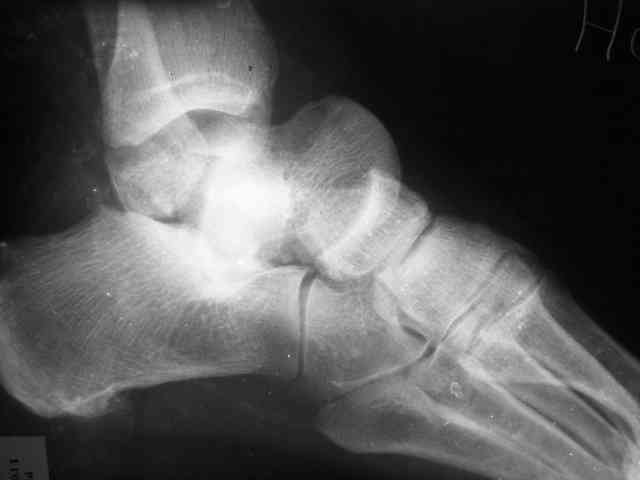

Уважаемый Александр! Как обещал представляю Р-граммы и операционные фото.

Опять надоедаю с вопросами:

Ваши (лично ваши) рекомендации - астрагалэктомия-аппаратный пяточно-большеберцовый артродез с одновременным удлинением голени - правильно?